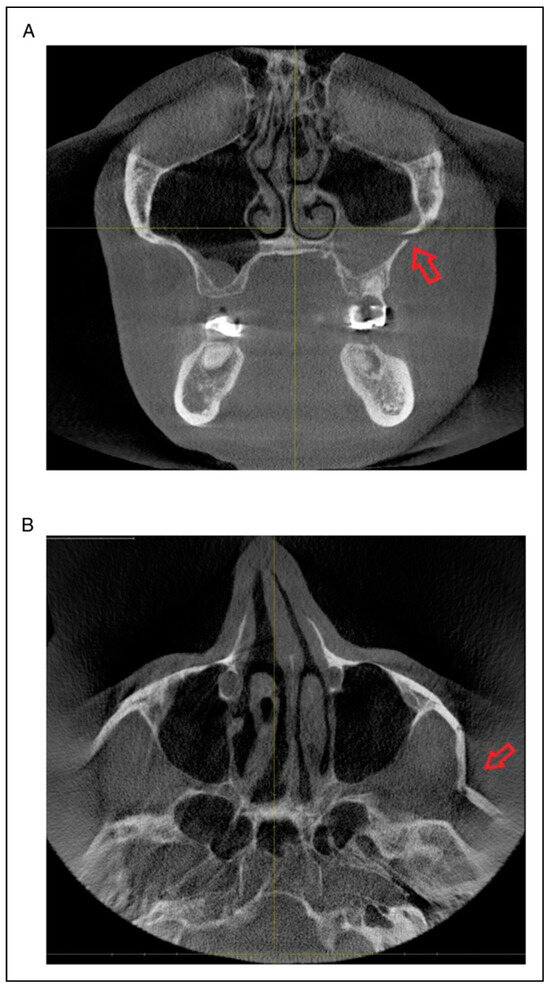

- Radiologic involvement of maxillary sinus wall and paranasal buttress fractures.

Fracture Prevalence of Maxillary Sinus Wall and Paranasal Buttress as Concomitance to the ZMO